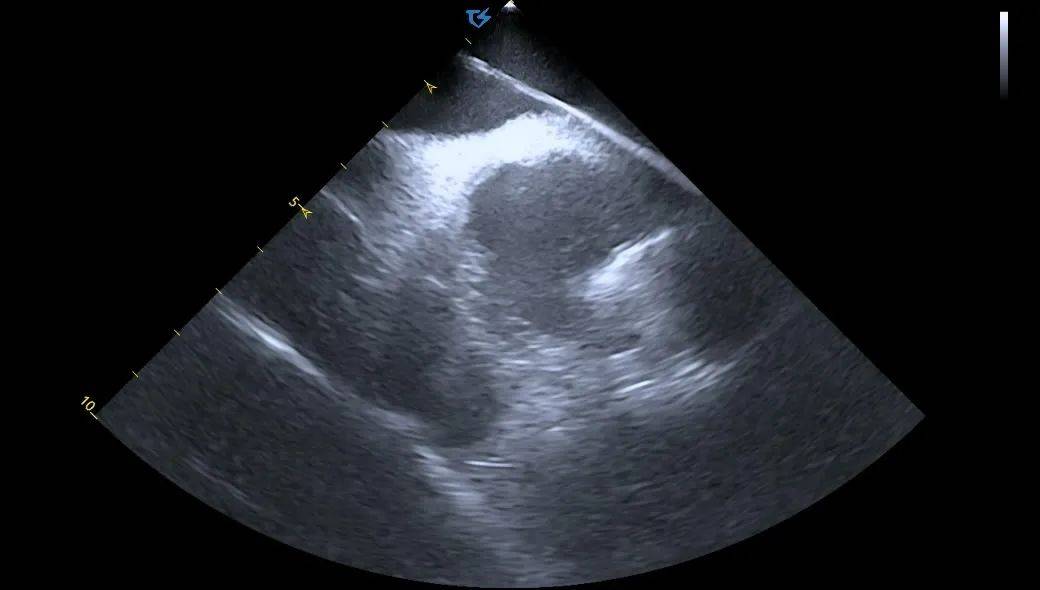

ICE引导消融导管位置:

血流模式确认左上肺静脉

血流模式确认左下肺静脉